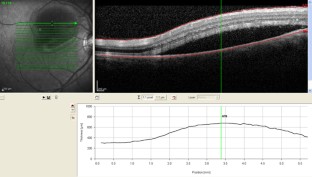

Abb. 2